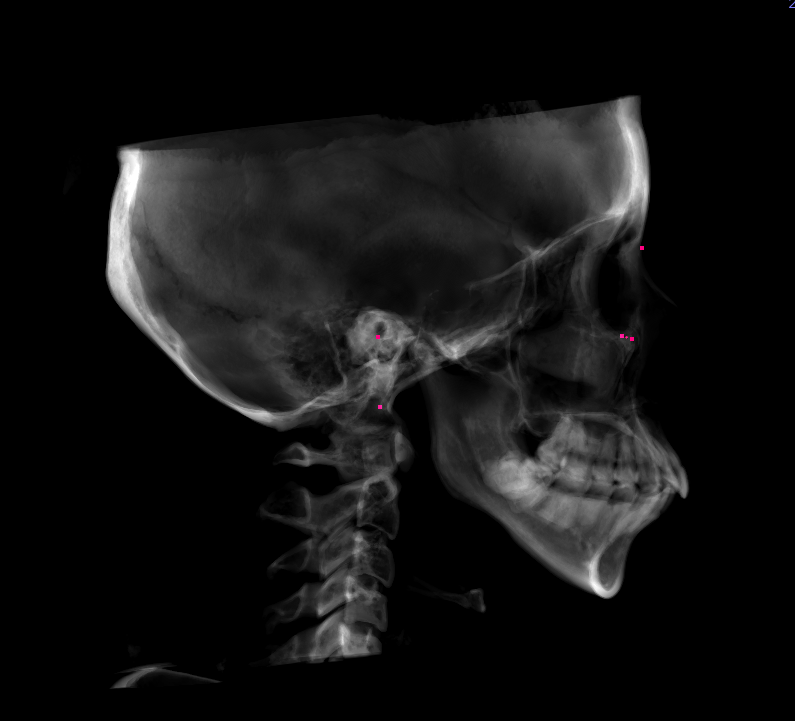

| 主訴 | 前歯のがたつきと出っ歯が気になる |

初診時の画像

確かにお顔を拝見すると、上の歯も下の歯もやや出ている感じがしますね。このような場合の治療法としては基本的には真ん中の歯の抜歯を行い、そのスペースを使用して、前歯をひっこめるのが定石です。もしくは少しずつ奥歯を後ろに移動し、さらに少し歯を削ることでスペースを作り前歯を後ろに引くのも一つです。大きく前歯をひっこめる場合にはやはり抜歯が妥当です。もう一つのご質問のマウスピース矯正で治療が可能かという質問ですが、それは可能です。しかし抜歯を行う場合には、マウスピース矯正だけでなくワイヤー矯正も併用する可能性があります。